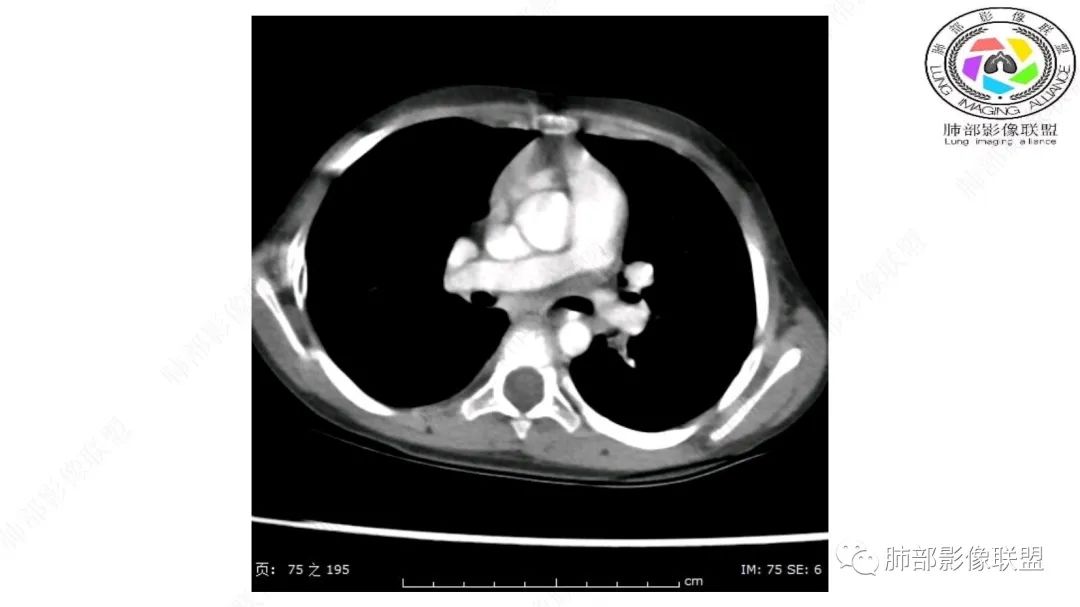

右上纵隔混杂密度肿块,边缘光整,与纵隔分界清,其内多发脂肪密度,增强无明显强化,其内血管穿行,考虑纵隔脂肪母细胞瘤,鉴别畸胎瘤,脂肪肉瘤。

右纵隔团状,密度不均,脂肪密度为主,内可见腺体样组织,类似乳腺,病灶边缘有分叶,与胸腺关系密切,增强后血管穿行。考虑胸腺脂肪瘤(不典型垂乳征),鉴别畸胎瘤。

三岁小儿,右侧纵隔巨大脂肪密度肿块,肺动脉穿行其中,密度欠均匀,未见明确实性成分,纵隔脂肪母细胞瘤,冬眠瘤鉴别纵隔脂肪增多症(多弥漫对称)。

患儿3岁 咳嗽检查发现纵隔占位。右肺上叶受压表现,占位以脂肪组织密度为主,似见分隔,首先考虑为脂肪母细胞瘤,鉴别脂肪瘤,畸胎瘤。

幼儿,右上纵隔团块状脂肪密度影,边缘清晰,内可见血管及支气管穿行,考虑脂肪瘤,鉴别畸胎瘤。

幼儿,右上纵膈团块,脂肪密度,内见分隔,增强病灶内见血管穿行,结合患者年龄,考虑脂肪母细胞瘤,鉴别脂肪瘤。

纵隔畸胎瘤,右前上纵隔团状脂肪密度?粘液样密度为主病变,病灶软边缘有分叶,内可见分隔,增强后血管穿行。3岁。考虑纵隔脂肪母细胞瘤,鉴别畸胎瘤。

病灶属于交界区,主体位于肺内,占位效应明显,前方突入胸壁,胸腺受压变形,胸膜显示欠清楚;病灶包绕上叶肺动脉;似乎有体动脉供血。符合肺内的点:包绕上叶肺动脉分支;符合纵隔的点:前方似乎突入胸壁,与胸腺关系比较密切,但是与上腔静脉的关系提示病灶不支持纵隔来源,前纵隔的常规会将上腔静脉受压后移、外移,这是不符合的。

手术记录:见右肺上叶肿物,肿物与右肺上叶关系密切。与纵隔无粘连,逐步分离肿物,见肿物大小约6cm*5cm,边界清楚,于右肺上叶粘连,边界清楚,肿物包绕右肺上叶血管及支气管。超声刀逐步游离肿物,完整切除肿物,右肺上叶肺组织无破溃,表面无出血。